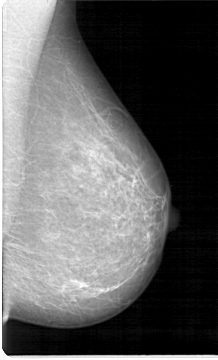

Refer to caption

Normal

Benign

InSitu

Invasive

Figure 3: Images of Breast Cancer Histopathology from the ICIAR2018 Dataset

Our network is trained and evaluated on three main datasets: BreakHis [4], containing 7,909 breast cancer histopathology images (2,429 benign and 5,429 malignant) at 40×, 100×, 200×, and 400× magnifications, each 700×460 pixels; Mini-DDSM [5], a reduced version of DDSM with approximately 2,000 annotated mammography images detailing lesion locations and diagnoses; and BACH from ICIAR2018 [6], with 400 HE-stained images in four categories (Normal, Benign, In-situ carcinoma, Invasive carcinoma), each 2048×1536 pixels. Fig. 2, 3, and 4 depict sample images from the BreakHis, ICIAR2018, and Mini-DDSM datasets. Tables I, II, and III also present statistical data for these datasets, including sample sizes and class distributions.